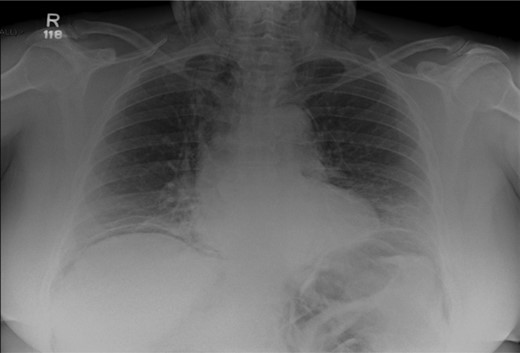

After her procedure she complained of swelling in her neck. This was not accompanied by shortness of breath, chest pain or abdominal pain. On examination, her oxygen saturation was 99% on room air, with normal respiratory and heart rate. Her respiratory examination was normal and her abdomen was soft and non-tender. She had marked crepitus over her clavicles, supraclavicular fossa and most of her neck. Her erect chest X-ray revealed air under both hemidiaphragms and significant pneumomediastinum (Fig. 1). A computed tomography (CT) scan of her chest, abdomen and pelvis was requested. This CT-scan revealed very extensive spreading of surgical emphysema in the retroperitoneum, extending into the mediastinum with small volumes of free intraperitoneal gas (Figs 2–4).

CT scan of abdomen showing free intraperitoneal gas compressing the splenic flexure.